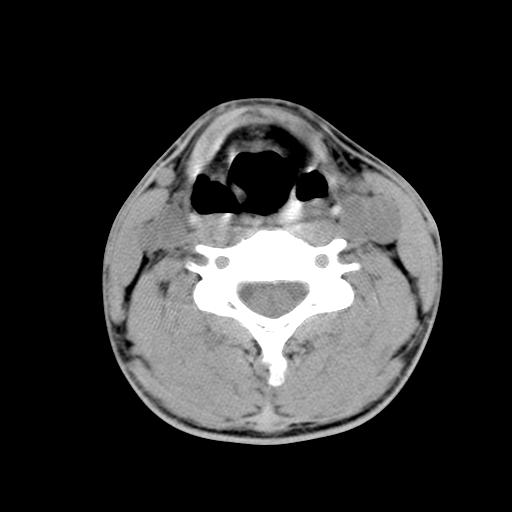

标题: CT15118:f-27y,左颈部肿一个月,无发热、无压痛 [打印本页]

标题: CT15118:f-27y,左颈部肿一个月,无发热、无压痛

1、甲状腺左叶病变:腺瘤?结节性增生?其他?

2、上极周围间隙病变。

3、2者关系?

左侧甲状腺肿大,密度不均.同侧甲状软骨似有破坏(建议传骨窗).左侧颈静脉增粗,各组织之间分界不清,有多个肿大淋巴结.甲状腺肿并感染?临床症状不符.淋巴结核?请结合其他检查.